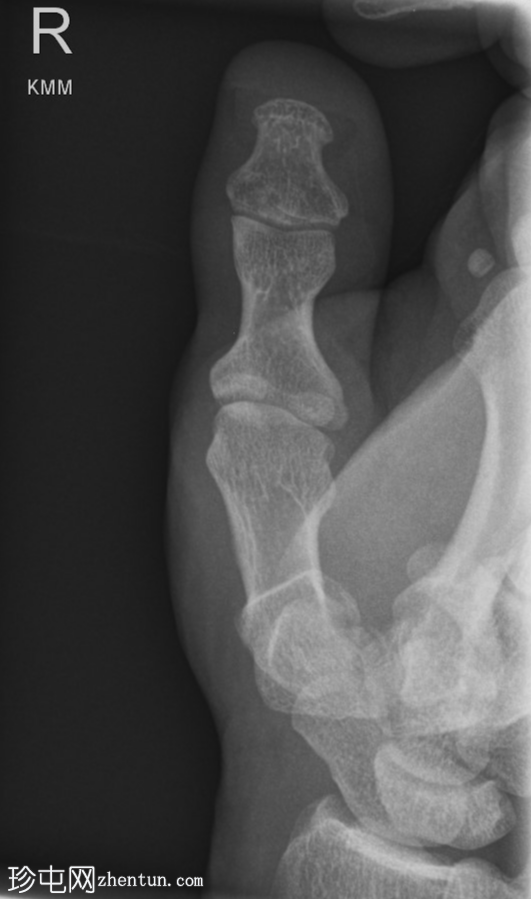

斜位

右拇指远节指骨掌侧关节内轻度移位骨折,可能为撕脱性骨折。关节内可见轻微皮质台阶。

第一掌骨基底部可见轻微移位骨折,根据骨折轨迹推测可能为关节内骨折,但关节内皮质台阶不明显。若临床治疗方案改变,可能需要进一步

影像

学检查。第一腕掌关节解剖对位良好。